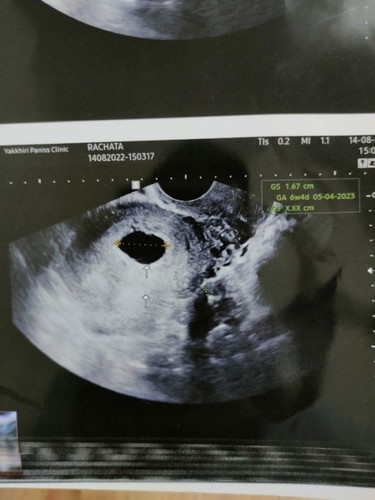

ถ้านับตามหมอแนกก้อประมาณ9ครับ แต่ในรูปมันระบุประมาณ6วีค ปจด แฟนปกติมีครั้งละ1-2วันเองครับ เลยนับไม่ค่อยแน่นอนเลยครับ

รอต่อไปอีกก่อนอายุครรภ์ยังไม่เริ่มมาก เพราะเด็กจะตัวเล็กมากๆๆๆๆๆๆคุณหมอจึงหาไม่เห็น เราก็เคยเป็นแบบนี้

พึ่ง 6 วีคเองค่ะแม่ ของแม่ก็ซาวหน้าท้องเจอแต่ถุงเหมือนกัน แต่พอไปอีกหมอซาวช่องคลอด เห็นตัวอ่อนค่ะ

รอดูอีกหน่อยน่ะค่ะบ้านนี้เจอน้องตอน8wตอนเราไปหาตอนนั้นน้องได้6wหมอก็บอกว่าอาจจะท้องลมตอนนี้น้องได้32wแล้ว

อย่าพึ่งหมดหวังนะคะ เราไปตรวจตอน6weekไม่เจอน้องเหมือนกันค่ะ แต่ตอนนี้ 17weekแล้วจ้า สู้ๆนะคะขอให้สมหวัง

เราซาวด์ครั้งแรกตอน7wไม่เจอน้อง เจอแต่ถุงตั้งครรภ์ กังวลมาก ซาวด์รอบ2 11wค่อยเจอน้องค่ะ

ของเราตอน 6w6d ก็ยังไม่เจอตัวน้องนะคะ คุณหมอนัดอีกทีตอน 8wค่อยเจอตัวน้องกับเสียงหัวใจค่ะ